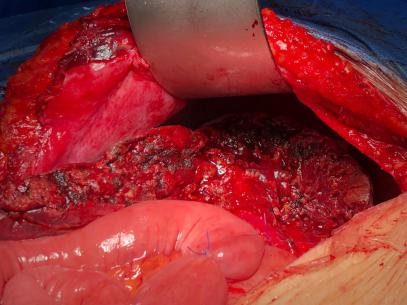

如解剖性精准肝叶、肝段切除,胰十二指肠切除,全胰腺切除,肝门部胆管癌根治(围肝门切除),胆管损伤修复,门脉高压断流、分流等。以下是部分手术图片。

7. 肝门部胆管癌根治,超左半肝切除+尾状叶切除,